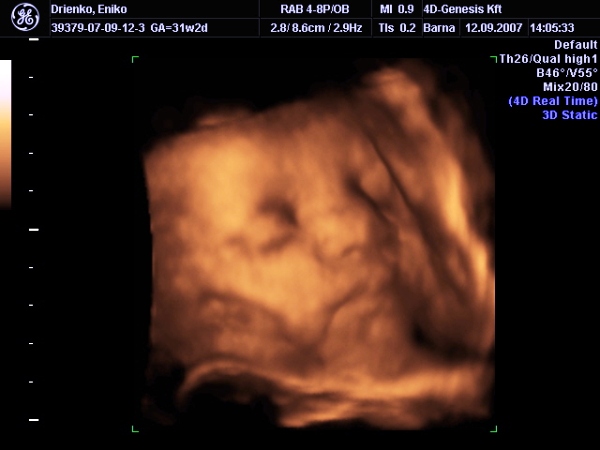

Itt vagyunk :D

Édes arcokat vágott, nyújtotta a nyelvét, grimaszolt, mosolygott :D El voltunk ájulva :) És akkkkora zacsija van, hogy dobtam egy hátast ;)

Csilla, köszi, igen, mondok címet, ahol aranyosak, meg látszik is a babó: II.ker., Lotz Károly u. 14. Genesis Kft. Asszem ez a nevük, tel. szám: 06 30 228 4444. 10500-ba kerül, ebben benne van a DVD és 2 fotó a babóról. Voltunk egy másik helyen is, de az kiábrándító volt, ezt tudom ajánlani.

Tesóka, a súlyát 1550re becsülte a gép (ha jól emlékszem), de oda van írva, hogy +-250gramm is lehet. A nő szerint nagyobb. :)

Igen, nagyon arin mutogatta magát, meg amikor a hátánál járt a szonda, akkor azt utálta, és jól megrúgdosta a vizsgálófejet ;) A nő egész megijedt :lol: